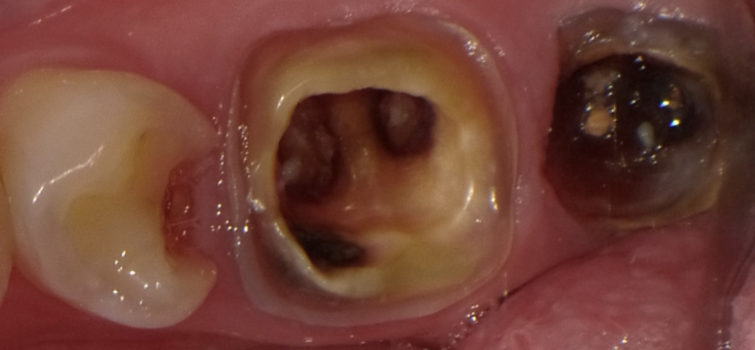

むし歯・根の病気(根尖病変)

むし歯の穴に詰まった汚れが細菌によって分解され、ニオイの原因になります。さらに虫歯が進行して神経が死ぬ(歯髄壊死)と、内部で細菌が増殖し、膿が溜まることで強い腐敗臭を伴うこともあります。